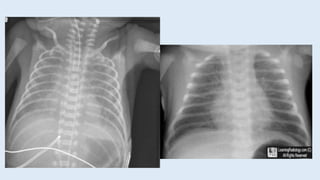

TTN Radiographic features

RDS Radiographic features

Radiograph Flat diaphragm; cardiomegaly;

sunburst pattern

Low volume; ground glass appearance

• #8 The characteristic findings on chest radiograph include increased lung volumes with flat diaphragms, mild cardiomegaly, and prominent vascular markings in a sunburst pattern originating at the hilum. Fluid often is seen in the interlobar fissures, and pleural effusions may be present. Alveolar edema may appear as fluffy densities. There are no areas of alveolar densities or consolidations

• #16 Chest radiography is generally obtained for all neonates with respiratory distress. The radiographic features of neonatal RDS (low lung volume and the classic diffuse reticulogranular ground glass appearance with air bronchograms) in a preterm infant with respiratory distress fulfill the clinical diagnosis criteria for RDS (image 1). (See 'Diagnosis' below.) Classic respiratory distress syndrome (RDS). Bell-shaped thorax is due to generalized underaeration. Lung volume is reduced, the lung parenchyma has a fine granular pattern, and peripherally extending air bronchograms are present.